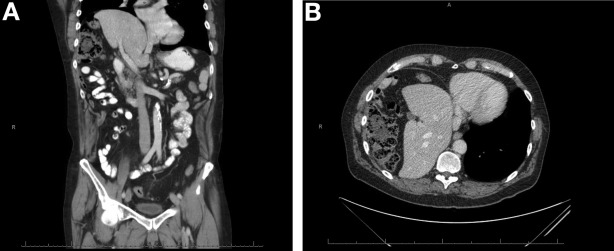

为进一步诊断,腹盆部CT扫描如图所示(图A,B)。

正确答案:间位结肠综合征

腹部CT图像显示间位结肠的标志,通常在肝曲,以及肝和右膈。这被认为是一个附带的影像学发现,一般无症状;然而,当出现临床症状如腹痛、腹胀、腹胀、厌食,便秘,或恶心时,它被称为间位结肠综合征。间位结肠综合征在一般人群中发病率为0.25%-0.28%。[2]

男性发生间位结肠综合征的概率是女性的4倍,且老年人中多见。间位结肠综合征的诊断需满足以下影像学标准:右膈必须高于肝脏,肠部必须被空气膨胀以表明假性气腹,肝脏上缘必须在左侧膈肌水平以下。[1]